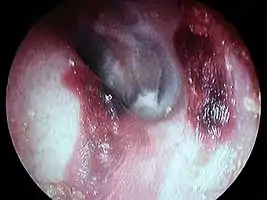

Hématome du conduit auditif externe gauche post coton tige

présence d'exostose dans le conduit auditif externe droit

- Hématome

- Exostose